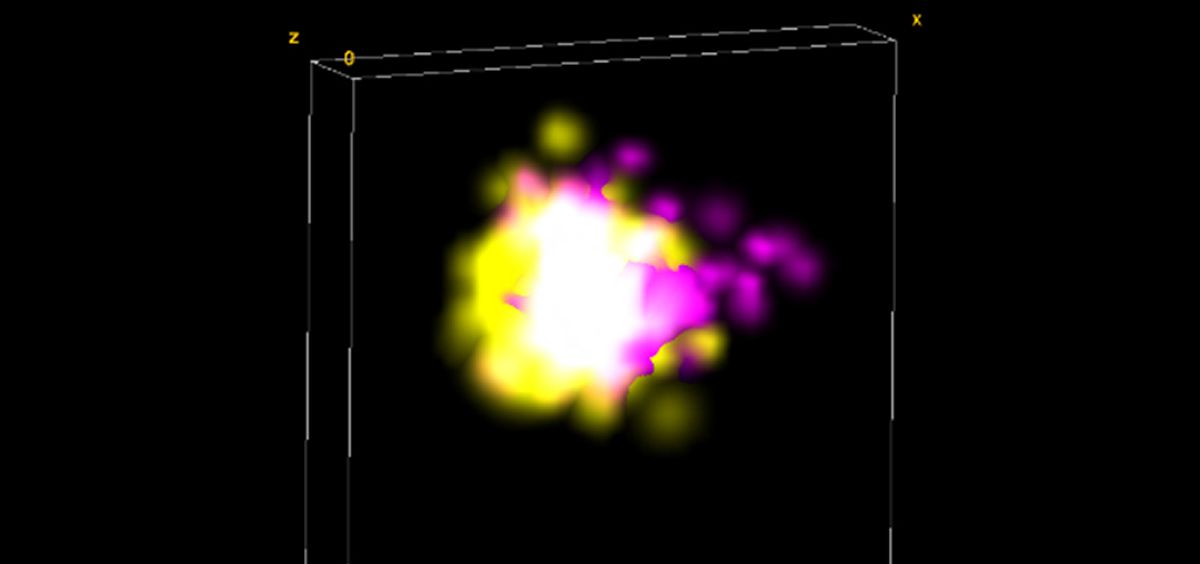

En la investigación se analizaron más de un millón de sinapsis de 42 personas, mediante técnicas realizadas con microscopios de gran potencia y resolución en colaboración con el IQAC-CSIC. Así, los investigadores visualizaron el flujo de proteínas dentro de las sinapsis individuales, observando que pequeños depósitos de la proteína Tau, conocidos como oligómeros, estaban en ambos lados de las sinapsis en personas que fallecieron de Alzheimer.

“Este estudio demuestra como la microscopia de super resolución, capaz de visualizar estructuras en la nanoescala, tiene mucho potencial en el estudio de los mecanismos moleculares implicados en las enfermedades”, explica Sílvia Pujals, investigadora del Ramón y Cajal del IQAC-CSIC.